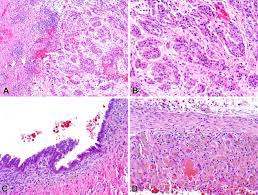

Diffuse malignant mesothelioma (dmm) is an uncommon cancer with great clinical significance because it currently remains an incurable disease, and most patients die within months after diagnosis. While many tumors have clear, defined edges, mesothelioma does not. The department of pathology, cork university hospital, cork, ireland (dr. mesothelioma can start in any location where mesothelial cells are normally found, although the most common location is in the parietal pleura. Another name for mesothelioma is malignant mesothelioma. mesothelioma is an insidious disease with long latency after asbestos exposure. During this process, the pathologist may also determine the mesothelioma cell type. Diagnostic criteria and proposed grading schema.

Subsequently, patients were classified into. Biphasic mesothelioma, epithelioid mesothelioma, desmoplastic mesothelioma, sarcomatoid mesothelioma. Sarcomatoid mesothelioma is shown with desmoplastic features. mesothelioma is an aggressive and deadly form of cancer. This study comprises 326 cases of sarcomatoid mesotheliomas among 2000. During this process, the pathologist may also determine the mesothelioma cell type. Weigh and measure in 3 dimensions. Malignant mesothelioma histology pathology outlines.